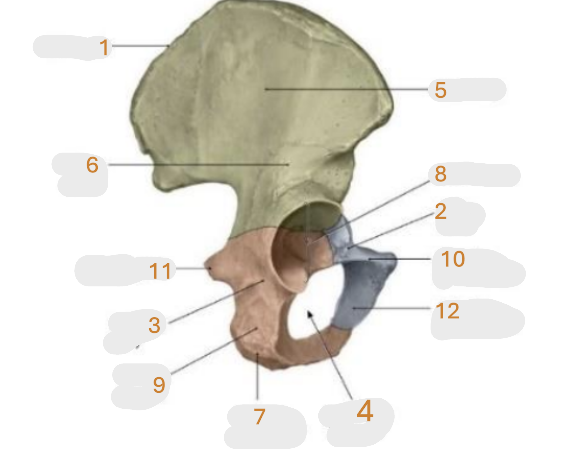

Where is the iliac crest

1

Where is the pubis body

2

Where is the ischium body

3

Where is the obturator foramen

4

Where is iliac wing

5

Where is the ilium body

6

Where is the ischial tuberosity

7

Where is the acetabulum

8

ischial ramus

9

Where is the superior pubic ramus

10

Where is the ischial spine

11

Where is the inferior pubic ramus

12